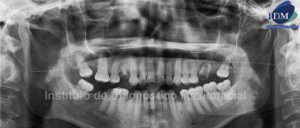

Paciente de sexo femenino y de 21 años de edad es referida al Instituto de Diagnóstico Maxilofacial para la evaluación de su estado dental y periodontal.